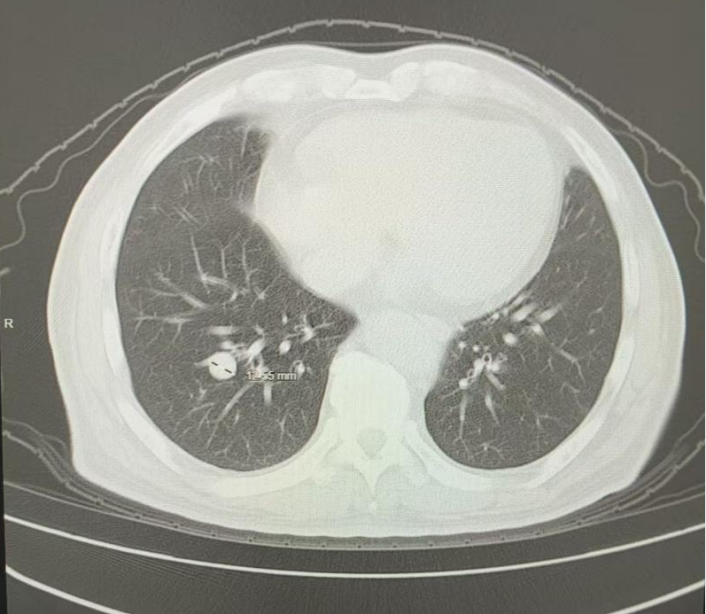

2025年3月(治疗后11个月),复查胸部CT:两肺多发结节,转移灶首拟,对比2024.12.16老片,右下肺结节略增大,疗效评估为SD

图5 患者治疗后11个月胸部影像学图像(2025年3月10日)

2025年5月(治疗后13个月),复查胸部CT:两肺多发结节,转移灶首拟,对比2025.3.10老片,右下肺结节似略饱满,疗效评估为疾病进展(PD),更换二线靶向联合免疫治疗方案

图6 患者治疗后13个月胸部影像学图像(2025年5月5日)